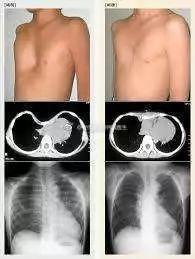

五、成人胸廓畸形的诊断

1. 体格检查:医生会通过观察和触摸来初步判断。

2. 影像学检查:比如X光、CT等,可以更清楚地看到胸廓的形状。